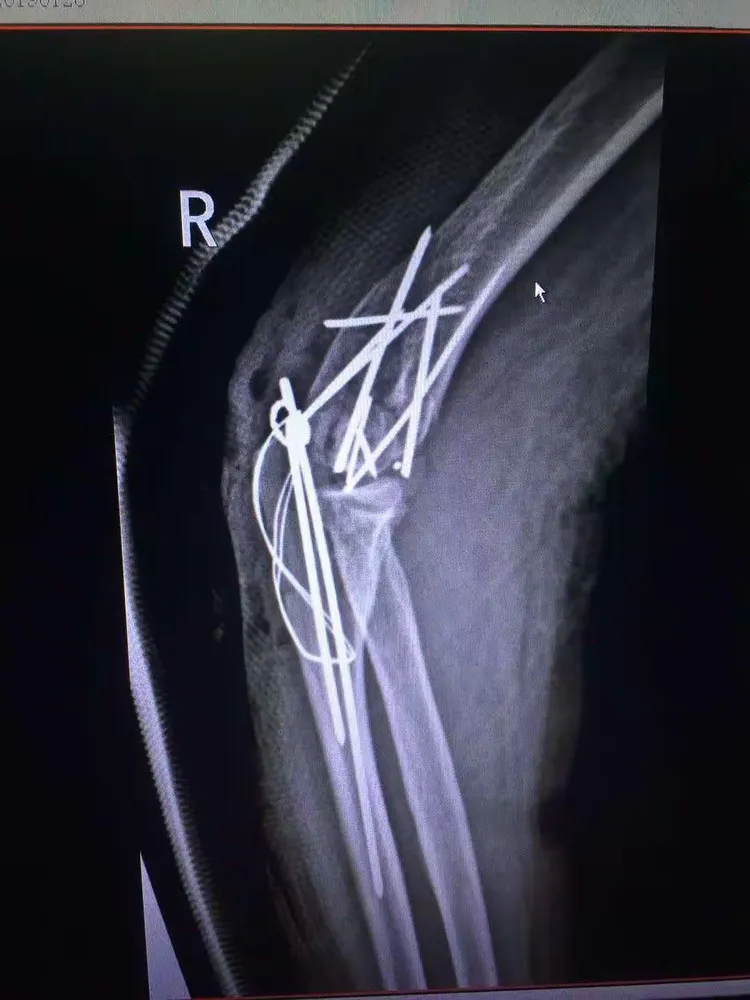

肱骨外髁骨折程度[s0]肱骨外髁骨折分型[s1]肱骨外髁骨折的临床表现[s2]肱骨外髁骨折Ⅲ型复位手法[s3]肱骨外髁骨折,保守治疗可以吗[s4]小儿肱骨外髁骨折[s5]儿童肱骨外髁骨折,医生不说你很可能永远都不会知道的[s6]不同类型的肱骨外髁骨折[s7]肱骨外髁骨折概述[s8]六、肱骨外髁骨折 - 图1[s9]六、肱骨外髁骨折 - 图2[s10]图片[s11]肱骨外髁骨折 m.haodf.com[s12]图片[s13]肱骨外髁骨折[s14]img[s15]肱骨外髁骨折.[s16]分期矫正儿童肱骨外髁骨折不愈合伴肘外翻畸形[s17]肱骨外髁骨折[s18]肱骨外髁骨折翻转90°,复位后克氏针或螺钉固定(自ao)[s19]右肱骨外髁骨折切开复位内固定术[s20]img[s21]img[s22]赵景新's media[s23]一例儿童右肱骨外髁骨折病例[s24]肱骨外髁骨折,保守治疗可以吗[s25]小儿肱骨外髁骨折[s26]肱骨外髁骨折固定[s27]肱骨外髁骨折 www.iiyi.com[s28]小儿肱骨外髁骨折的诊断和治疗[s29]右肱骨内外髁骨折[s30]图36-48 肱骨外髁骨折的不同程度移位 a型无移位;b型中度移位;c型完全移位伴旋转[s31]肱骨外髁骨折 www.haodf.com[s32]肱骨外髁骨折 www.haodf.com[s33]问:左肱骨外髁骨折,左肘关节脱位,6.[s34]儿童肱骨外髁骨折 - 小红书[s35]儿童肘关节损伤之--肱骨外髁骨折[s36]▲右侧肱骨外髁骨折闭合复位克氏针固定及石膏固定术后。“幸亏在掉落的[s37]肱骨外髁骨折 www.guahao.com[s38]肱骨头及外髁骨折,求诊治方案,手术还是非手术[s39]